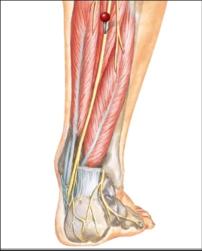

The red pins in the bottom picture point out the nerves in the top pictures. As you can see different nerves travel to different parts of the foot, top, bottom, sides and toes. By isolating the exact location of neuropathy we can isolate the nerve involved.

Diagrams courtesy of Netter's Anatomy